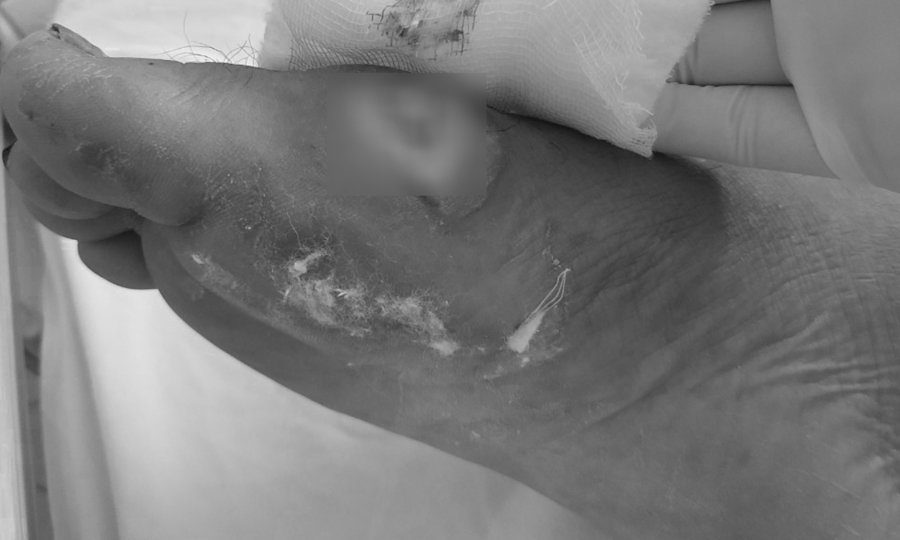

Chân bệnh nhân bị hoại tử do vi khuẩn Burkholderia. Ảnh: Bệnh viện cung cấp.

Sau đợt bão lũ kéo dài từ đầu tháng 10 đến nay, số ca nhiễm bệnh Whitmore ở nhiều tỉnh miền Trung ngày càng gia tăng. Quảng Trị ghi nhận 24 ca, Bệnh viện Thừa Thiên-Huế tiếp nhận 30 ca … Bệnh viện Đà Nẵng điều trị 29 ca, bệnh nhân chủ yếu đến từ Quảng Nam, Nghệ An, Quảng Ngãi và Đà Nẵng. – Vết thương do áp xe do Whitmore gây ra đã được điều trị. Ảnh: Bệnh viện cung cấp.